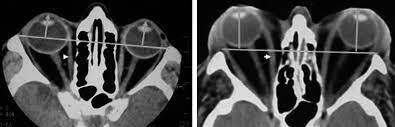

¿Cuáles son los hallazgos radiológicos en la TC del exoftalmos?

¿Qué es la disociación índice globo ocular?

Es la diferencia en la distancia del ojo izquierdo con el derecho